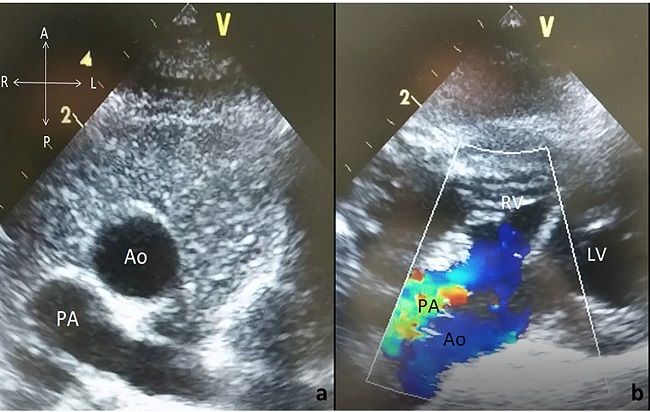

A 15-day-old newborn male was referred to our clinic for further evaluation of central cyanosis and previously detected heart murmur. Prenatal history was unremarkable with uneventful full term labour. During the initial physical examination, the baby was slightly cyanotic (SpO2: 88-90%) and the cardiac auscultation revealed a grade II systolic murmur at the upper left sternal border. Four extremity pulses were regular with approximate blood pressure results. The electrocardiogram was consistent with possible right ventricular hypertrophy and the chest X-ray demonstrated cardiomegaly due to enlarged right cavities, flat pulmonary trunk segment, and diminished pulmonary vascular markings. The transthoracic echocardiography revealed situs solitus, levocardia with normal pulmonary venous drainage, and atrioventricular concordance. Ventriculo-arterial relations were supplied by both the entire pulmonary trunk emerging from the right ventricle along with more than 50% of the aorta. DORV with anterior and left-sided aorta was evidenced (Figures 1A and 1B). Secundum type atrial septal defect of 10 mm in two-dimensional images maintaining left to right shunt, subaortic VSD approximately 9 mm in diameter with mostly left to right bidirectional flow, and right ventricular outflow tract obstruction originating from the subvalvular region generating a transpulmonic gradient of 50 mmHg were also noted. Both the left and right ventricular systolic functions were evaluated as preserved. There was no obstruction of the aortic arch and the pericardium had a normal appearance. For more detailed evaluation of the cardiac anatomy, cardiac computed tomography was performed (Figures 2A and 2B). The final diagnosis was DORV with situs solitus, D-loop ventricles, and L-position of the aorta {S,D,L}, left aortic arch associated with a large subaortic VSD, and pulmonary stenosis. Although the weight gain of the patient was sufficient with an uneventful follow-up, decremental course of the systemic saturation clarified the necessity of a surgical intervention at the age of six months. Surgery was performed via standard median sternotomy, and ascending aortic + bicaval cannulations were initiated afterwards. Anatomical relationship between the great vessels and intracardiac defects was coherent with the echocardiography. Additionally, juxtaposition of the right atrial appendage to the left and the sinus node artery passing through the anterior aspect of the right ventricular epicardium were also noticed perioperatively. DORV repair, including the Rastelli procedure (VSD closure with porcine pericardium, right ventricle-pulmonary trunk conduit: 14 mm Contegra® Medtronic, Inc. Medtronic Parkway Minneapolis, United States of America) and cessation of the antegrade flow by over-and-over suture technique, was performed. The postoperative course was uneventful, and the patient was discharged from the hospital on the postoperative 10th day. The proceeding follow-ups were free of problems.